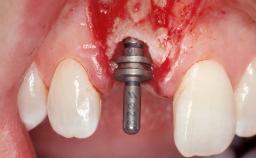

Late Flapless Placement of an Implant in a Maxillary Left Central Incisor Site

A 39-year-old male patient presented with a chief complaint of discomfort and gingival discoloration around his maxillary left central incisor. He was in good general health and was a non-smoker. His past dental history was significant because of the traumatic fracture of tooth 21 in a sporting accident at age 13. Initial dental treatment included endodontic therapy and a full-coverage restoration. The patient became symptomatic 5 years later, when structural failure of the tooth resulted in the dislodgment of the crown. Endodontic retreatment, apical surgery, and post-and-core restoration were performed.

Type of Implants One-Piece

Attachment One-Piece

Placement Protocol Early or late implant placement

Bone Volume Deficient horizontally, requiring prior grafting

Esthetic Risk High